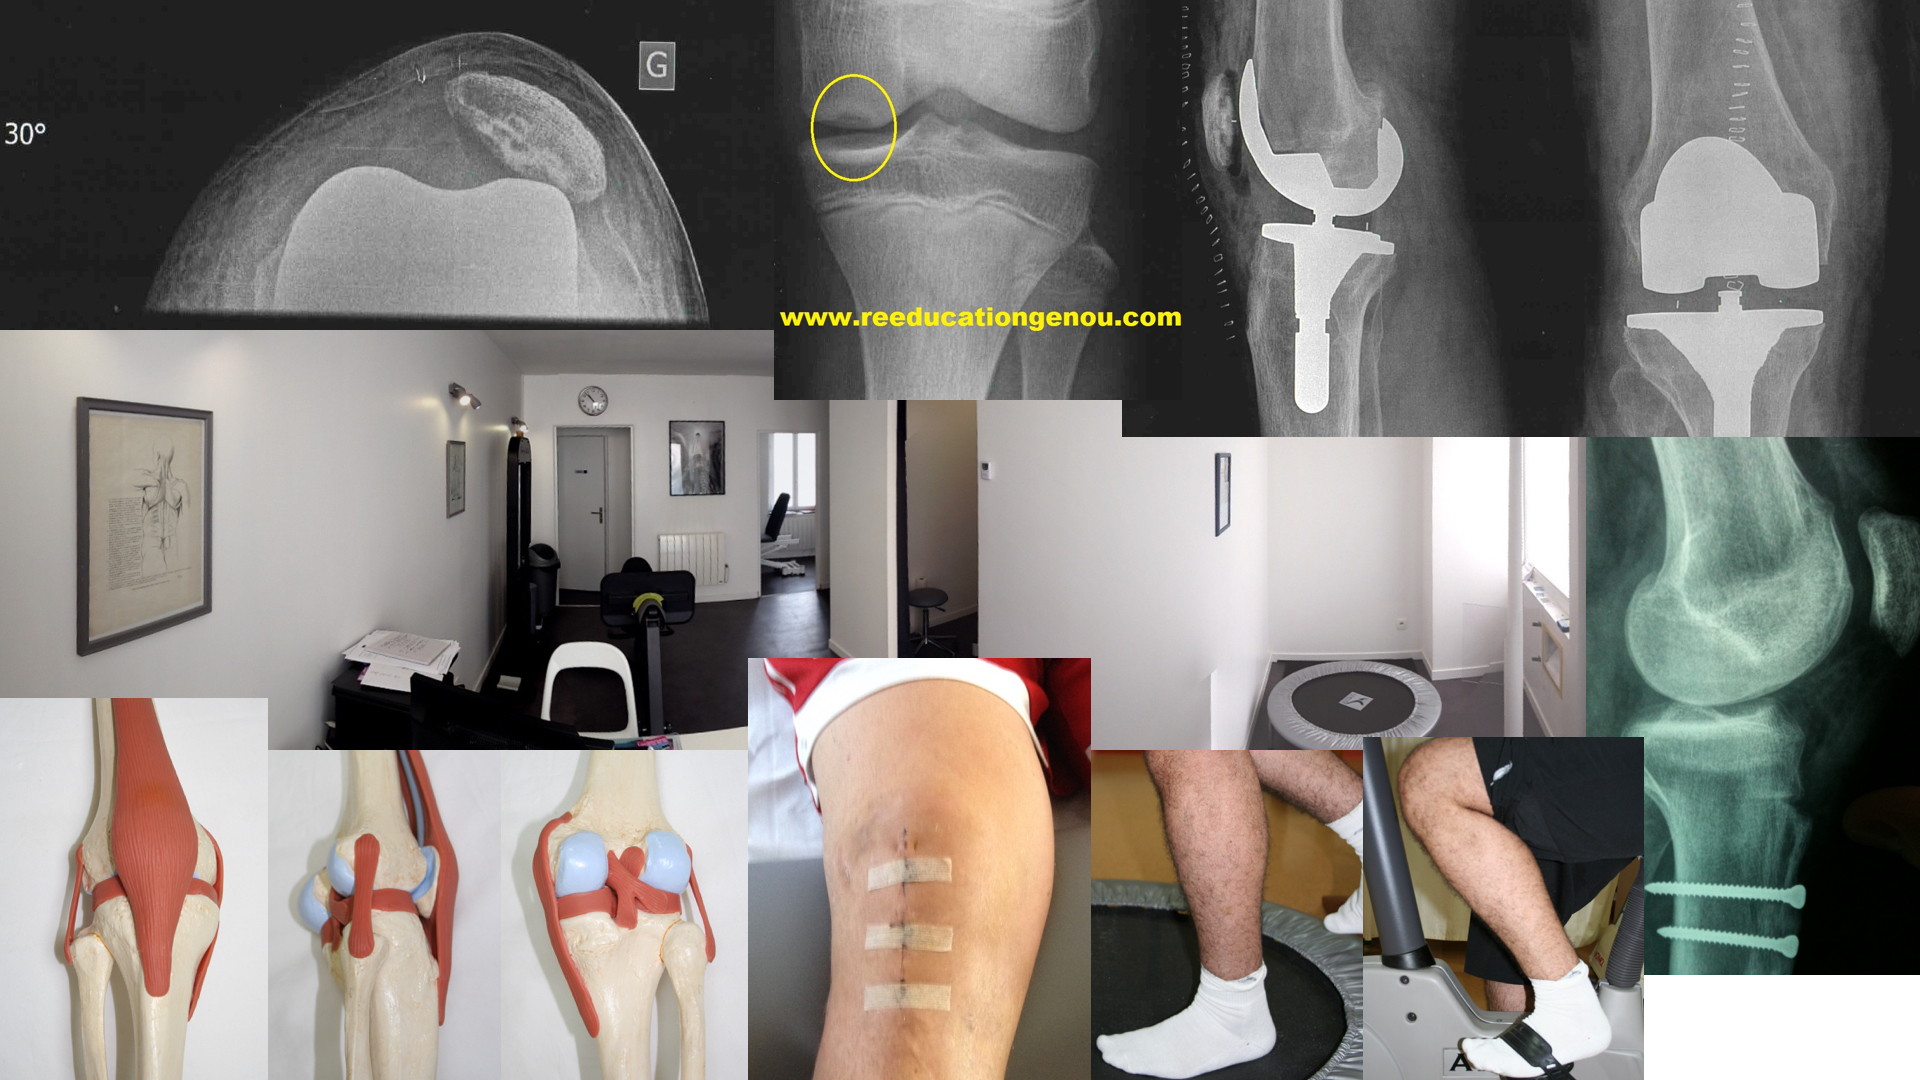

• Soit ce déficit est prévu par l'ajout d'une suture méniscale ou une réparation ligamentaire / musculaire soit la sensation en fin d'extension est dure et douloureuse...Ce dernier cas qui frole les 1,5% des genoux n'obtenant pas l'extension à 2 mois post-opératoire peut être la conséquence d'un CYCLOP SYNDROME.

• en cas de doutes il faut tester la qualité de la fin de l'extension. si c'est un point dur que l'on retrouve ajouté à un flexum cela peut effectivement être un cyclope. Donc avis chirurgical

• Le cyclope syndrome est rare, il limite l'extension du genou parfois jusqu'à 20° de flexum par hyper-cicatrisation= kyste autour du pied de la plastie du LCA. La fin d'amplitude d'extension est ressentie par le kiné comme dure et inextensible. La solution, dont la décision revient au chirurgien seul peut être une arthroscopie pour nettoyer tout ça, enlever le kyste ce qui libère de suite l'extension et la flexion complète.